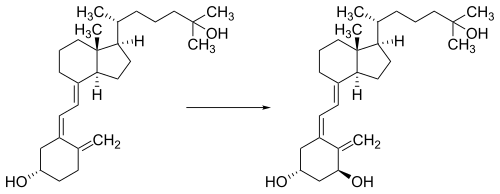

Whether synthesized in the skin or ingested, vitamin D is hydroxylated in the liver at position 25 (upper right of the molecule) to form the prohormone calcifediol, also referred to as 25(OH)D).[3] This reaction is catalyzed by the microsomal enzyme vitamin D 25-hydroxylase, the product of the CYP2R1 human gene.[203] Once made, the product is released into the blood where it is bound to vitamin D-binding protein.[204]

Calcifediol is transported to the proximal tubules of the kidneys, where it is hydroxylated at the 1-α position (lower right of the molecule) to form calcitriol (1,25-dihydroxycholecalciferol, also referred to as 1,25(OH)2D).[1] The conversion of calcifediol to calcitriol is catalyzed by the enzyme 25-hydroxyvitamin D3 1-alpha-hydroxylase, which is the product of the CYP27B1 human gene. The activity of CYP27B1 is increased by parathyroid hormone and also by low plasma calcium or phosphate.[1] Following the final converting step in the kidney, calcitriol is released into the circulation. By binding to vitamin D-binding protein, calcitriol is transported throughout the body.[14] In addition to the kidneys, calcitriol is also synthesized by certain other cells, including monocyte-macrophages in the immune system. When synthesized by monocyte-macrophages, calcitriol acts locally as a cytokine, modulating body defenses against microbial invaders by stimulating the innate immune system.[205]